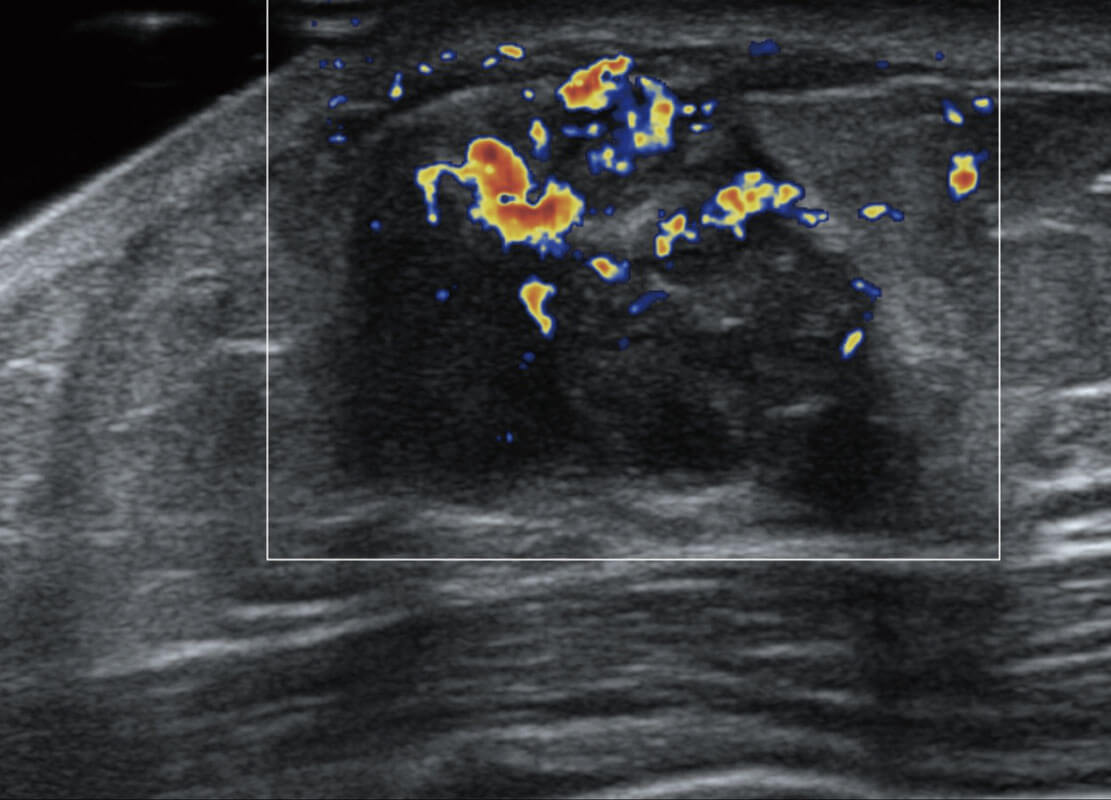

乳腺导管癌

乳腺癌显微血流

P60搭载宽频带线阵探头、宽景成像、弹性成像技术,为您提供乳腺应用方案。P60支持高频相控阵探头、线阵探头、腹部高频探头、腹部微凸探头等,丰富的探头群搭载敏感的彩色血流成像,适用于新生儿多种脏器检测要求,满足新生儿筛查需求。